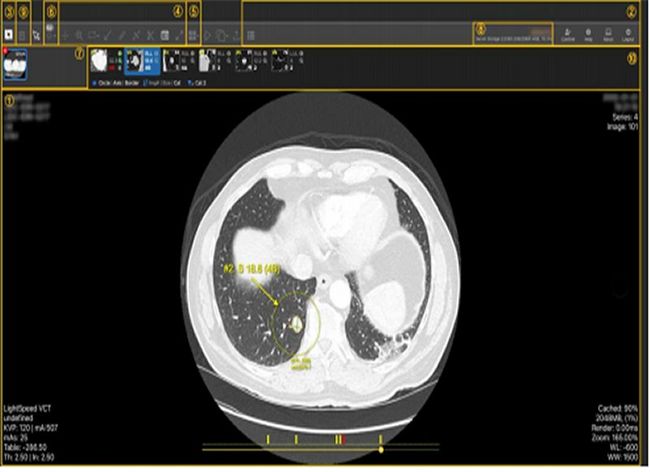

`2023년 상반기 우수연구개발 혁신제품으로 신규 지정된 `폐 CT의 폐암 조기진단을 위한 폐결절 검출 보조진단 시스템`

주요 제품으로는 건강·의료분야의 폐암 조기진단을 위한 ‘CT영상 판독시스템’과 복부 대사질환의 위험도를 예측하는 ‘AI 기반 대사질환 분석 시스템’ 등이 있으며, 안전·재해예방 분야는 ‘다목적 휴대용 방사선 오염측정기’와 ‘감염성 폐기물 밀봉포장 처리기’, 가스누출을 자동감지해 화재·폭발사고를 예방해주는 ‘다기능 loT 가스콕’ 등이 있다.